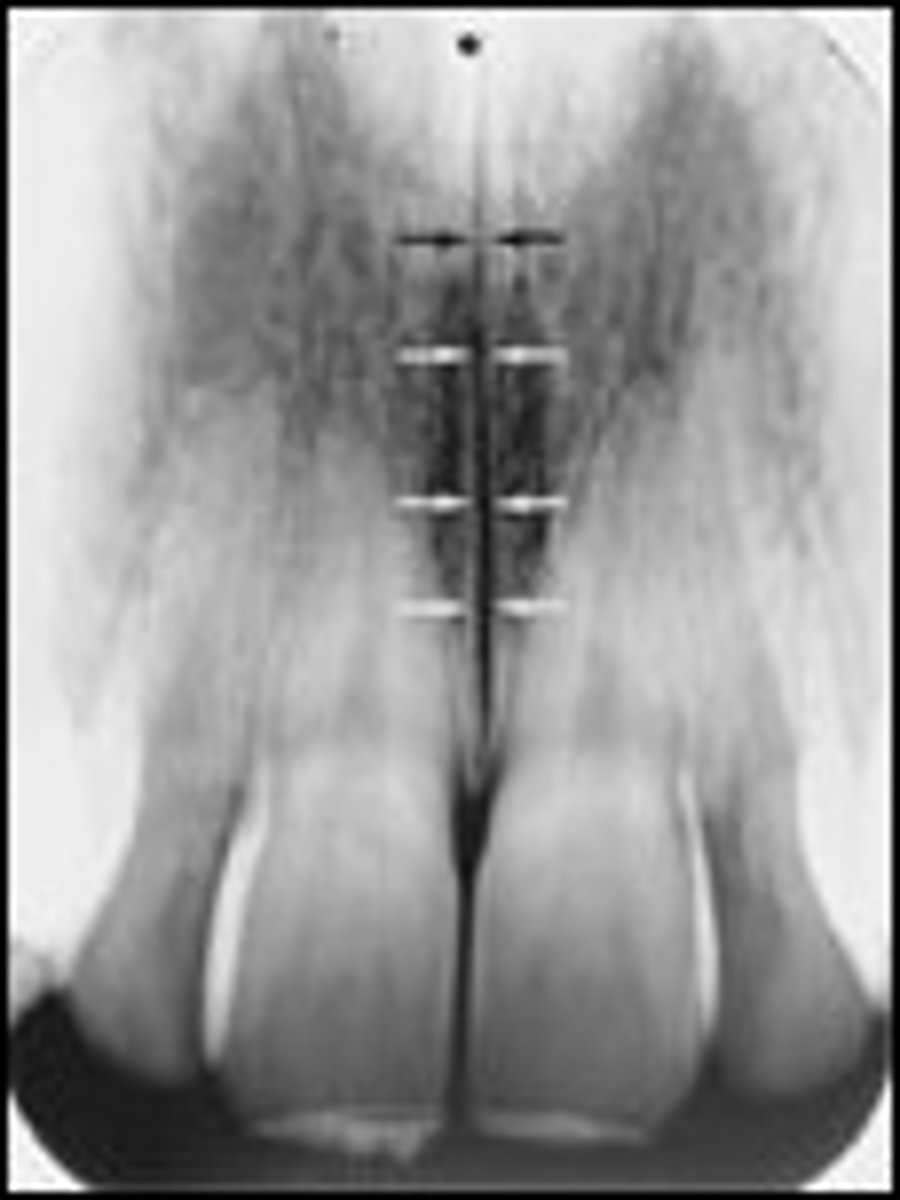

Nutrient canals

What is the radiolucent structure seen here?